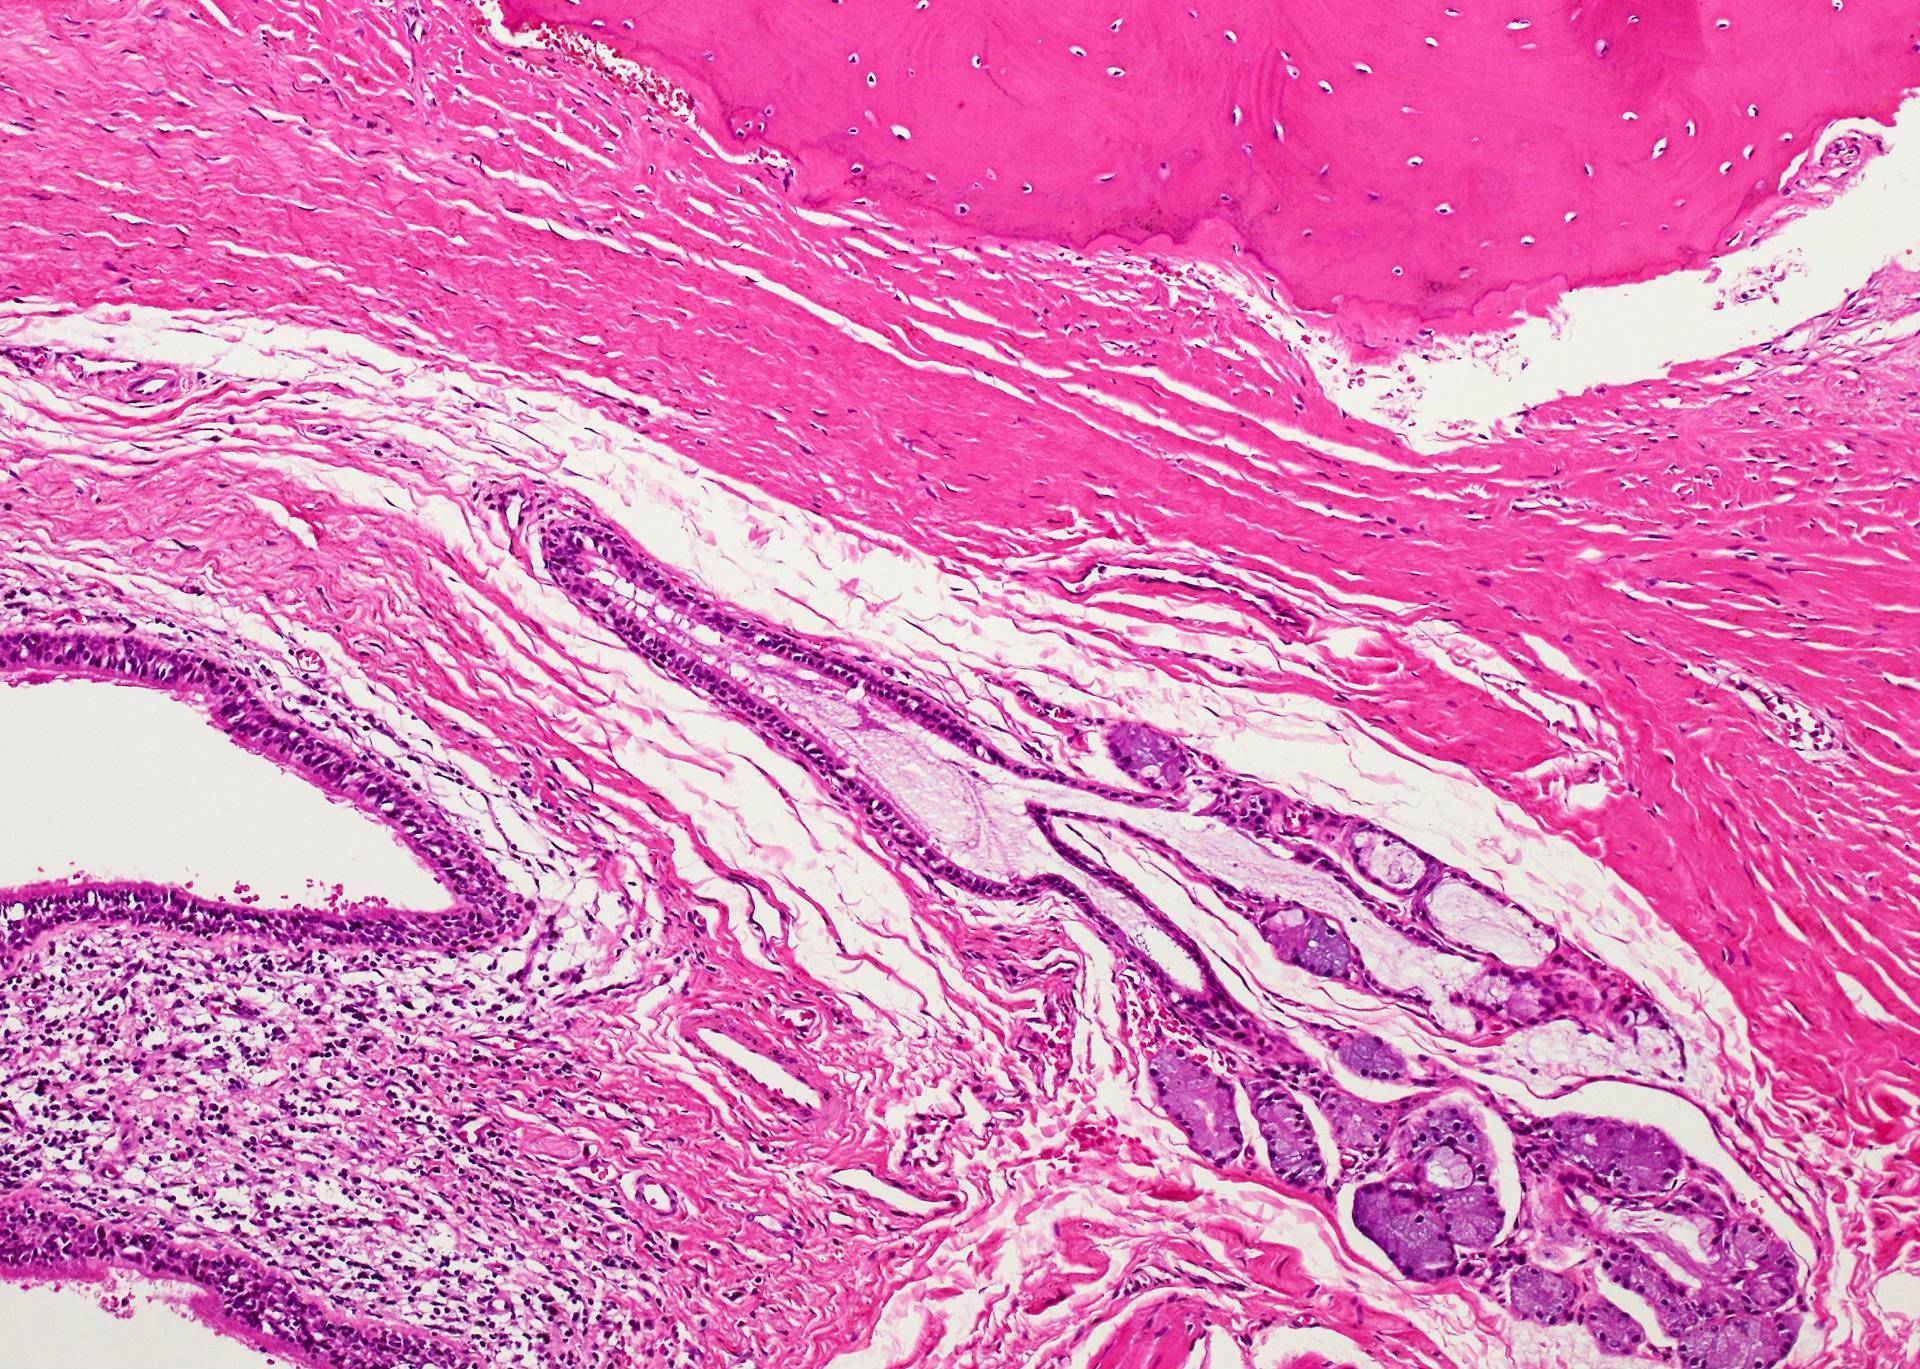

Microscopic (histologic) description

- Type of epithelial lining varies by site, and combinations of the types below can be seen in a single cyst (Head Neck Pathol 2013;7:50):

- Ciliated pseudostratified columnar (respiratory) epithelium in lower neck, perhaps due to its close proximity to upper respiratory tract

- Nonkeratinizing squamous epithelium in higher neck (near tongue and foramen cecum), also can be of metaplastic origin in inflammatory settings

- Stratified cuboidal epithelium at level of hyoid bone

- Very often the cyst is denuded of epithelium, at least focally, which reflects epithelial damage by inflammation

- Secondary inflammation is common, especially in sinus tract (J Pediatr Surg 1984;19:506):

- Intense lymphocytic infiltration, rarely arranged into lymphoid follicles

- Admixture of neutrophils (if the cyst is infected)

- Granulation tissue and fibrosis

- Thyroid follicles in the cyst / duct wall:

- Found in 30% - 60%, with higher yield on serial sections

- More common in infra- versus suprahyoid remnants, on the right paramedian side (Ann Otol Rhinol Laryngol 2000;109:1135)

- Seen in small irregular groups

- Thyroid epithelium may be normal or rarely hyperplastic or neoplastic

- Thyroid tissue often hidden by inflammation (Laryngoscope 2001;111:1002)

- Absence of thyroid tissue does not exclude the diagnosis of TGD cyst

- Mucous salivary-type glands can be found in the cyst wall, frequently in lingual and suprahyoid locations (Ann Otol Rhinol Laryngol 1996;105:996)

Microscopic (histologic) images

Contributed by Andrey Bychkov, M.D., Ph.D., Mark R. Wick, M.D. and AFIP